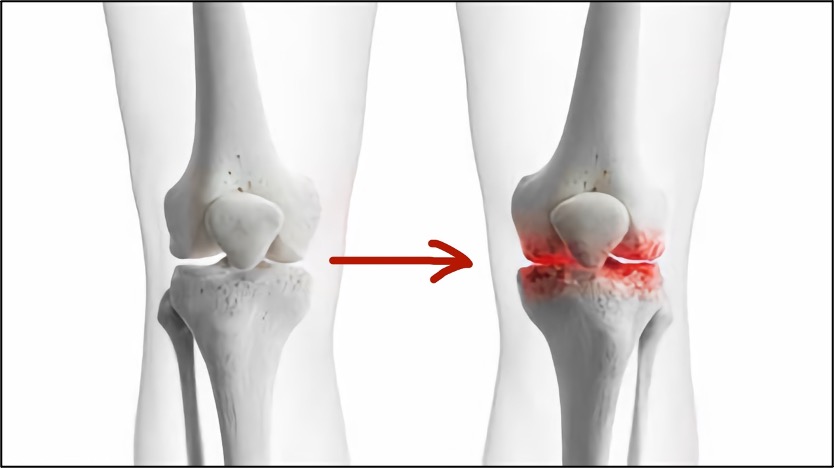

失去了前交叉韧带的关节,前后以及旋转不稳定,关节总是晃来晃去,必然导致关节内其它结构,如半月板,软骨的磨损,不仅在运动时反复扭伤,而且在日常生活中也会不断地磨损着关节,导致关节退变,也就是机器老化。

加速关节退变,导致“机器提前老化”

如果长此以往,哪怕是你不再运动,关节退变的速度也会比正常情况下快得多,最后的结果是:你在30岁、40岁时,关节却已经老化到了六七十岁,走个路都疼、肿胀。到了那种地步再来手术或者治疗就已经没有任何意义了!唯一能做的就是关节置换手术了!